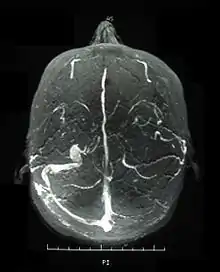

![]() | |

| A person with hypopyon which can be seen in anterior uveitis in a person with Behçet's disease | |